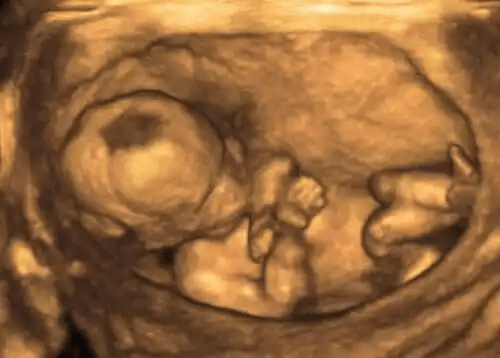

Lekarze zwykle wykrywają te zmiany za pomocą procedury ultrasonograficznej w celu pomiaru objętości płynu owodniowego. Robią to poprzez wyznaczenie indeksu płynu owodniowego (AFI).

Aby uzyskać te informacje, ekspert dzieli macicę na cztery niezakłócone ćwiartki, której głębokości mierzy w centymetrach. Normalny AFI wynosi od 8 do 21 cm.